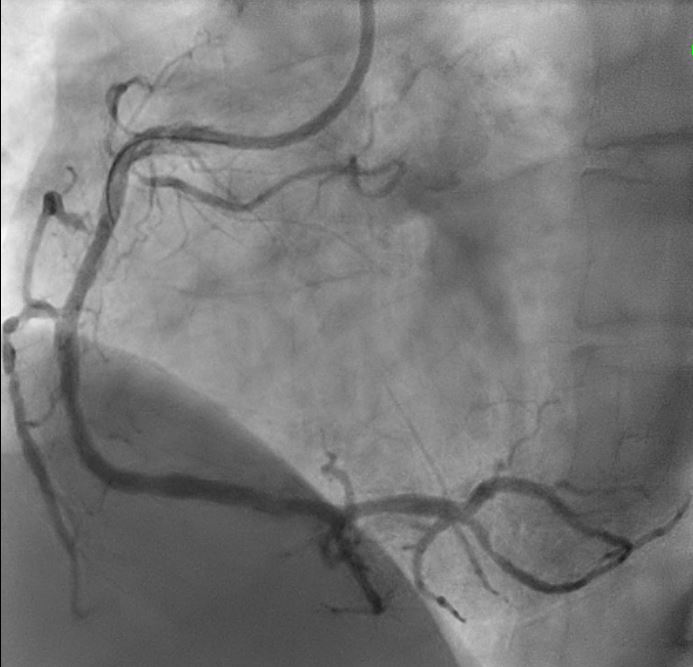

Initial engagement with a JR3.5/6Fr guiding catheter provided suboptimal support; this was switched to a SAL 0.75/6Fr guide, which offered only modest improvement. Lesion predilatation was performed with non-compliant balloons (0.85/15 mm and 1.5/15 mm) assisted by a guide extension catheter. Intravascular ultrasound (IVUS)revealed a distal reference vessel diameter of 3.0 mm and proximal reference of 3.5 mm, with evidence of white thrombus at the mid RCA. Further lesion preparation was performed using Naviscore balloons (3.0/15 mm distally and 3.5/15 mm proximally),achieving satisfactory luminal gain. A repeat IVUS run confirmed resolution of the white thrombus. Based on this, a drug-coated balloon(DCB)-only strategy was chosen. EssentialPro DCBs (2.0/40 mm for distal-mid segment, and 3.5/40 mm for mid-proximal segment) were successfully delivered and deployed. Post-procedure IVUS demonstrated significant improvement in minimum lumen area (MLA)—from 2.91 mm©÷to 4.07 mm©÷ (distal) and 1.60mm©÷ to 6.93 mm©÷ (proximal).

This case underscore severe important learning points. Firstly, intravascular imaging is invaluable in guiding interventional strategy — from assessing thrombus burden and vessel size to confirming adequate lesion preparation and luminal gain. Second, with careful lesion preparation and confirmed thrombus clearance, a DCB-only PCI strategy can be considered a feasible alternative to DES implantation in selected cases. Finally, early recognition and aggressive lipid-lowering therapy are critical in suspected familial hypercholesterolemia to prevent further atherosclerotic progression.